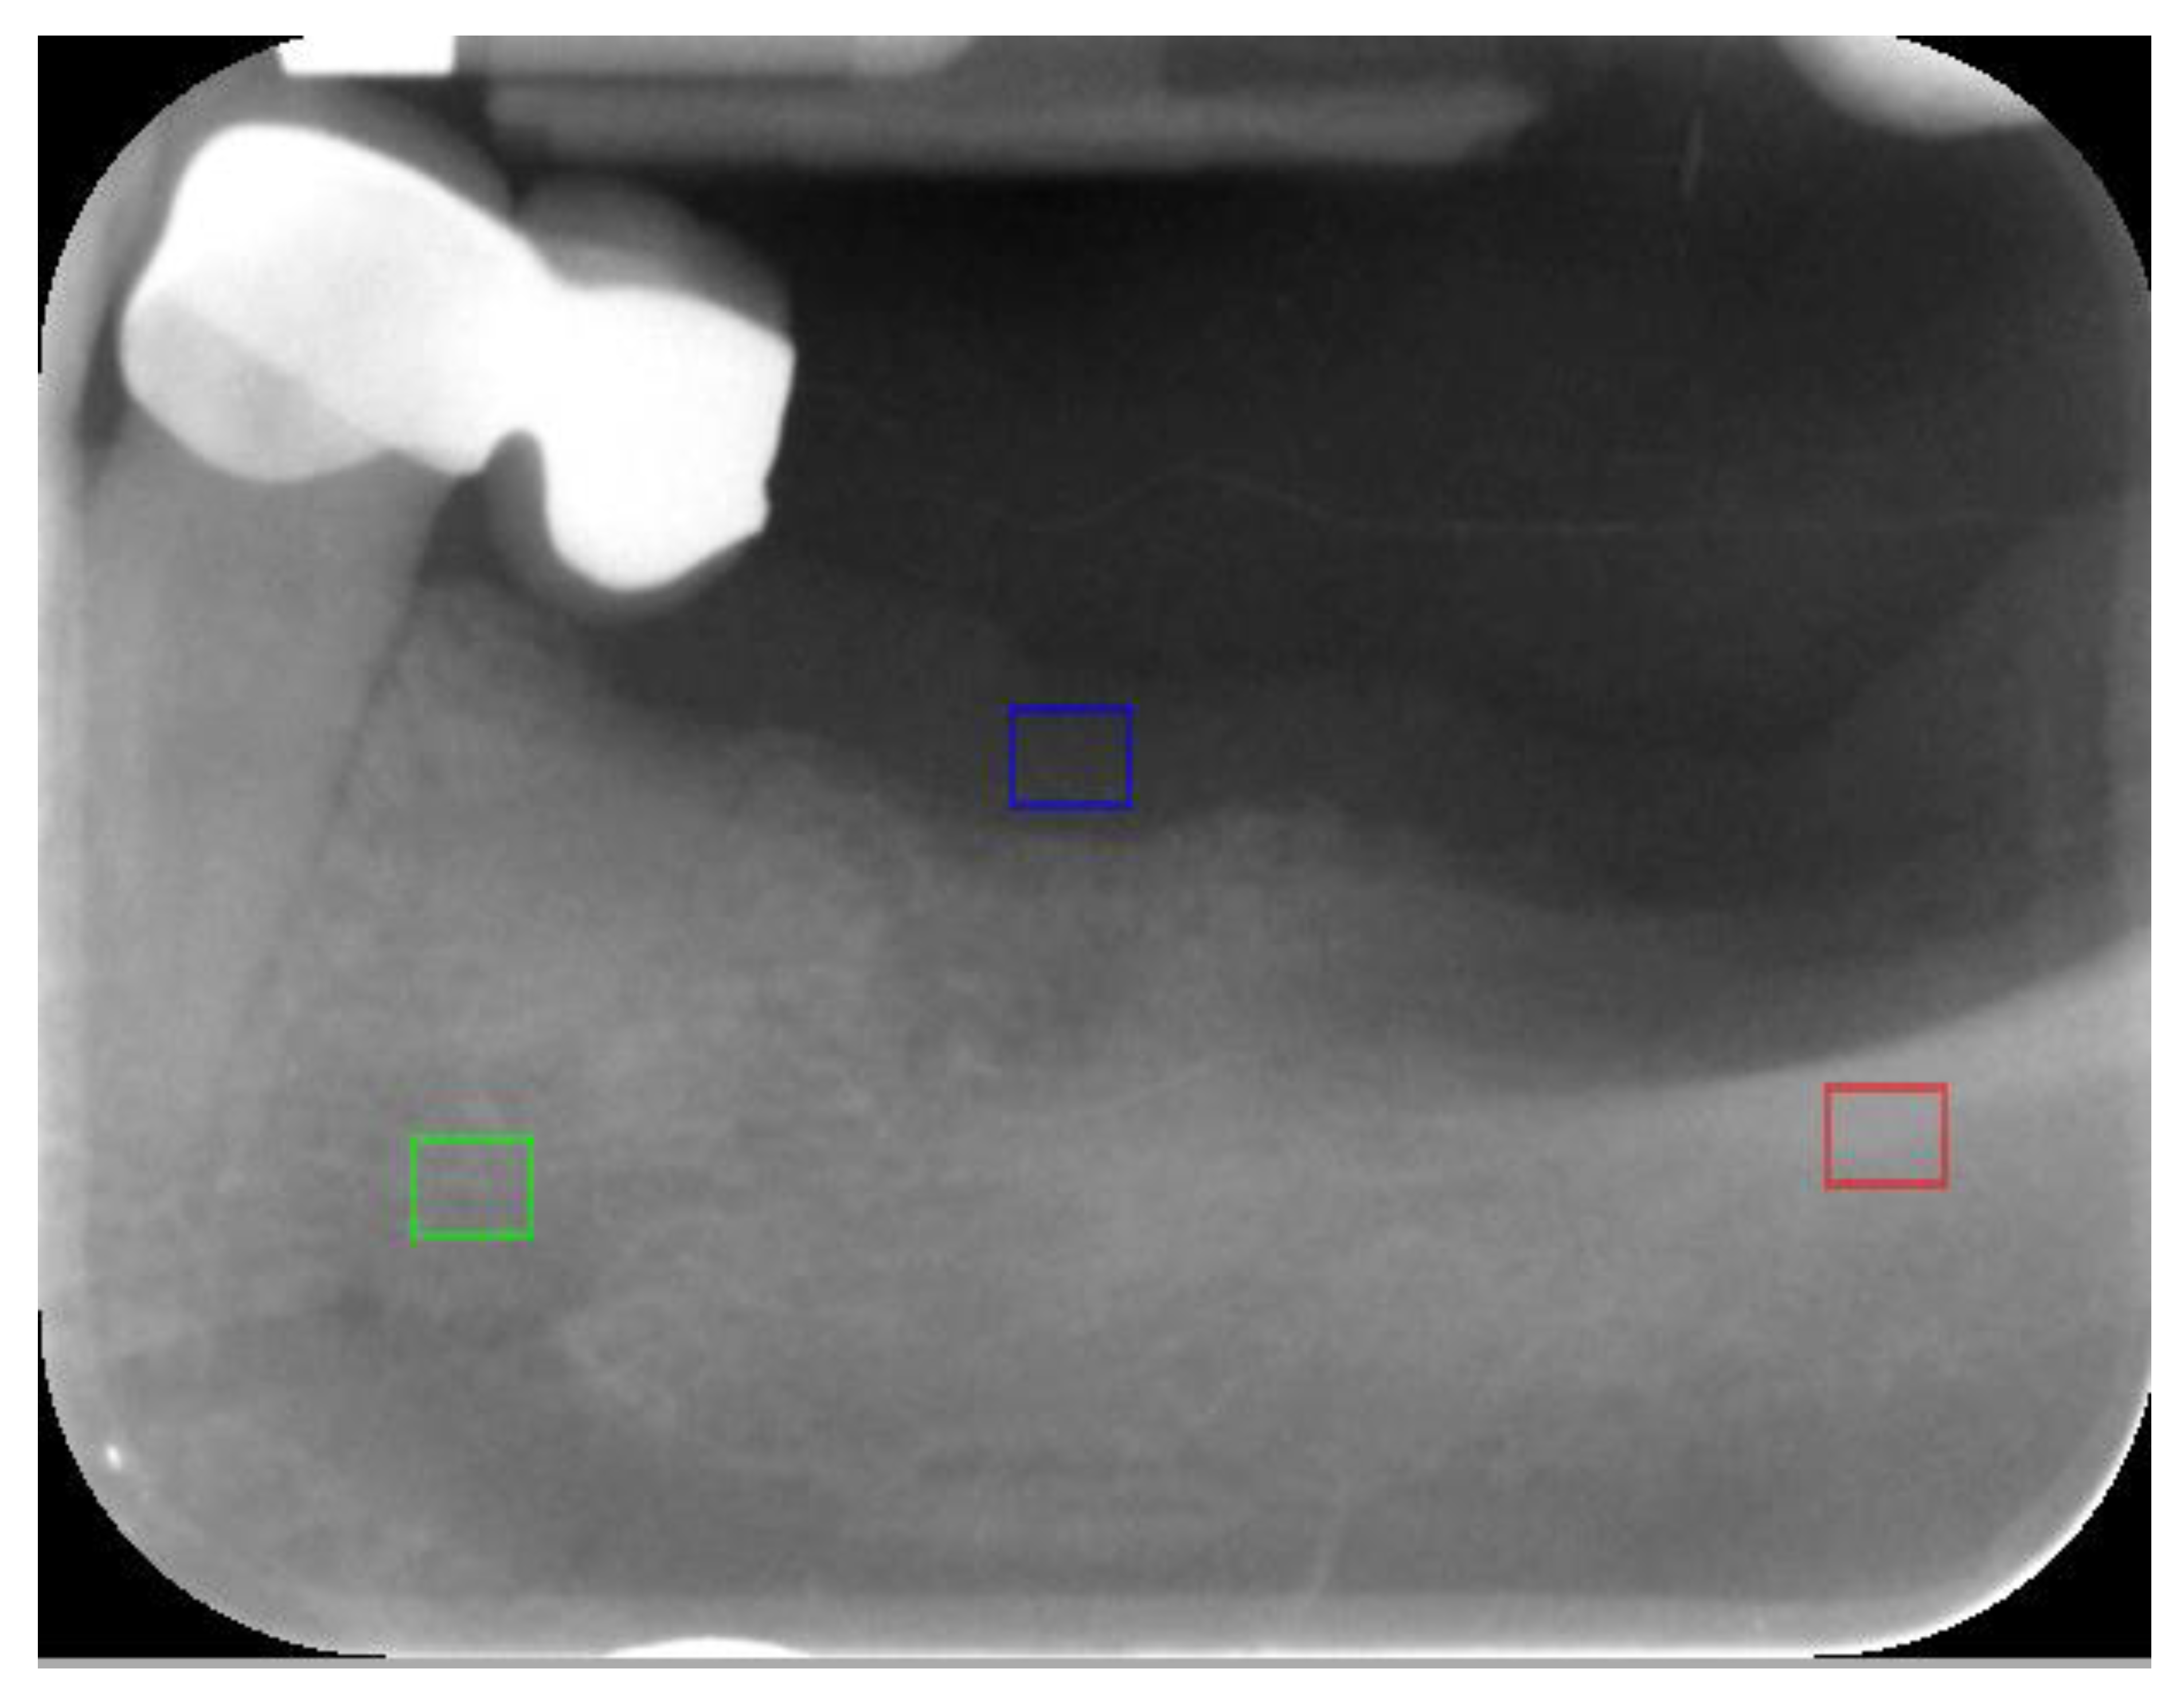

A preliminary investigation was performed to evaluate which values of the textural features describe the cortical bone, trabecular bone, and soft tissue as a reference. Thirty samples from each of these regions of interest (ROIs) were analysed (Figure 1).

Figure 1.

Regions of interest (ROI) marked for reference: cortical bone (red ROI), trabecular bone (green ROI), and soft tissue (gingiva) (blue ROI).